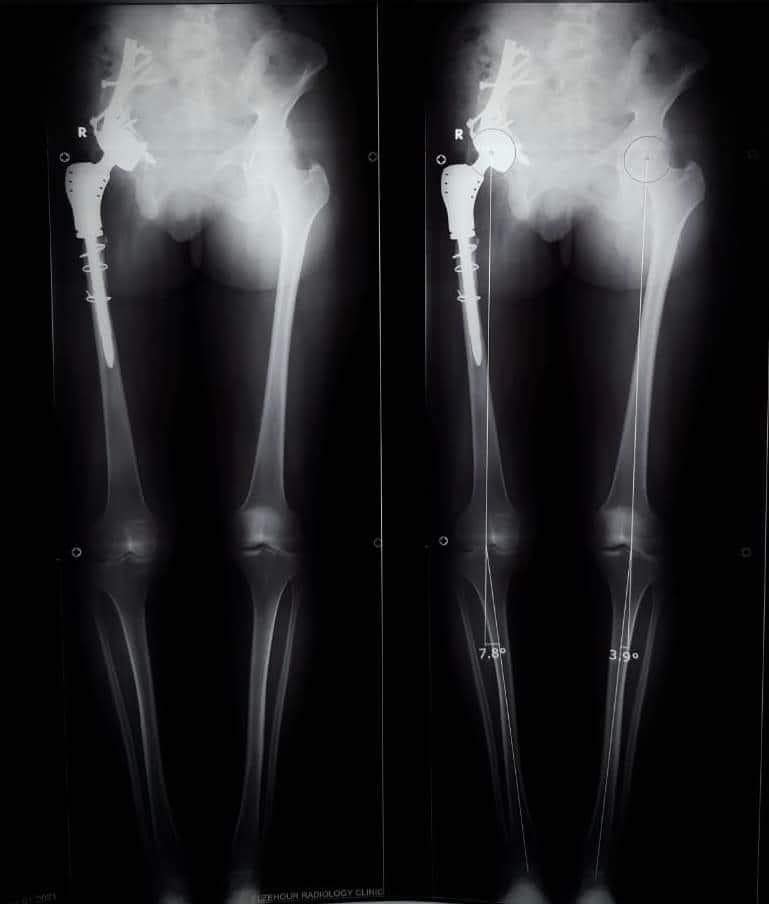

وأوضح الدكتور عمرو السيد علي أستاذ جراحة العظام، واستشاري الجراحات الميكروسكوبية جامعة أسيوط، أن المريضة تبلغ من العمر 15 عامًا، وكانت تعاني من وجود ورم في عظمة الآلية، ومفصل الحوض؛ مشيرًا إلى إجراء العملية الجراحية على مرحلتين في إطار زمني 3 شهور؛ لتجنب البتر؛ حيث تم في المرحلة الأولى إزالة الورم من عظمة الآلية، ونقل الجزء العلوي من عظمة الفخذ؛ لتحل محل عظمة الآلية.

وأوضح الدكتور محمد مهران أستاذ جراحة العظام المساعد، واستشاري جراحات تغيير المفاصل الصناعية جامعة أسيوط، أنه تم -بعد إجراء الفحوصات الطبية- تركيب مفصل صناعي كامل ذي مواصفات خاصة للحوض، وذلك دون اللجوء لتثبيت المفصل، ولتجنب البتر لهذا الطرف؛ مشيرًا إلى نجاح العملية واستقرار الحالة الصحية للمريضة، وتمت متابعتها؛ لحين عودة حركة المريضة لصورتها الطبيعية، مشيرًا في الوقت نفسه أنه تم نشر العملية الجراحية عالميًا: في مجلة علمية متخصصة للحالات الصعبة؛ بمساعدة الدكتور أحمد عادل خليفة مدرس جراحة العظام بكلية الطب جامعة جنوب الوادي.